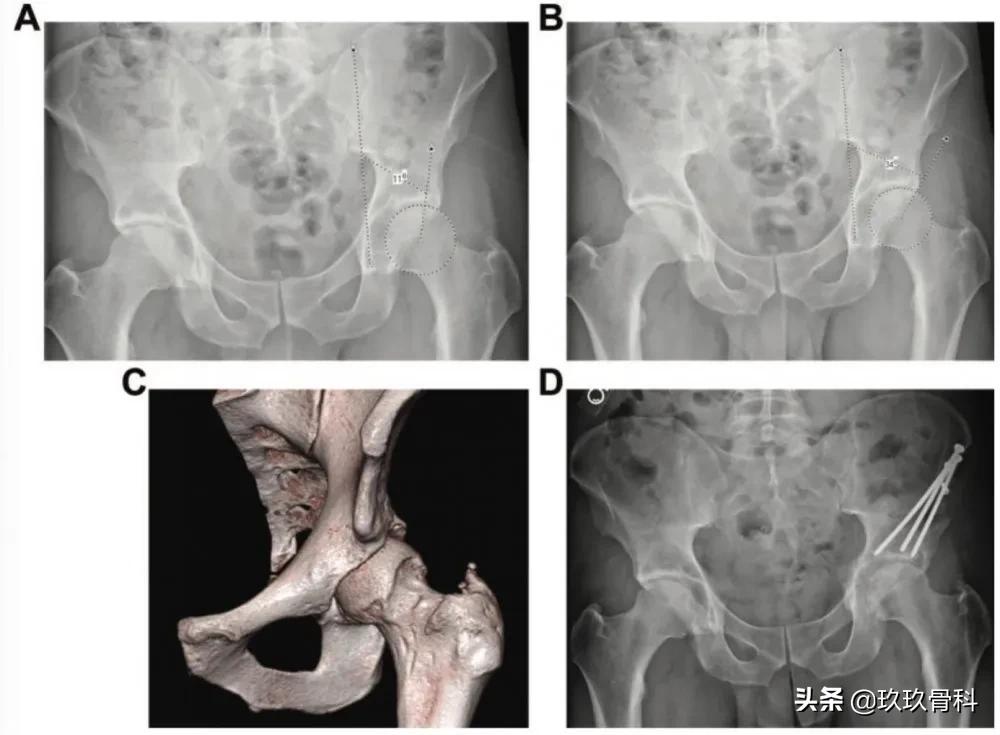

30岁男性髋臼成形、盂唇修复和股骨骨软骨成形术后。(A)站立前后位(AP)骨盆X线片显示髋臼前上方切除过度,由此产生的硬化缘外侧中心边缘角(LCEA)为11°,(B)骨缘LCEA显示为34°。(C) 三维CT重建显示髋臼从12点到2被切除。(D) 髋臼周围截骨术治疗医源性发育不良的骨盆X线片。